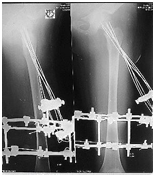

Excellent union was achieved within 3 months (Figure 2-5).

Figure 2 Delbet type-II.

Figure 3 During treatment with Ilizarov frame.